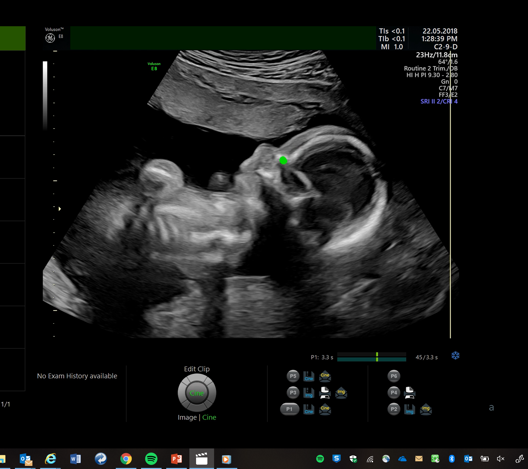

Perception Ultrasound by Learning Sonographic Experience

PULSE is an ambitious, innovative, interdisciplinary research project exploring the use of artificial intelligence-based technologies to reduce the need for highly trained ultrasound operators. We apply the latest ideas from machine learning and computer vision to build, from real-world ultrasound scanning videos, eye-tracking and probe movement data, computational models of visual search and navigation. These models describe how an expert sonographer performs a diagnostic study of a patient from multiple perceptual cues. By building models that more closely mimic how a human makes decisions from ultrasound images, we aim to demonstrate that we can build considerably more powerful assistive interpretation methods than have previously been possible from analysis of ultrasound images and videos alone.